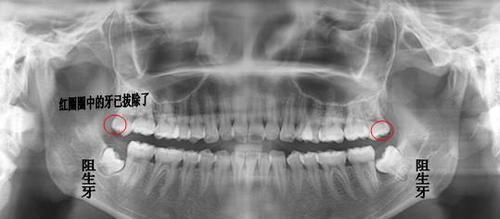

2 如果出现了阻生智齿,也就是说前面的牙齿阻碍了智齿生长的话,需要拔掉,因为有可能会造成对位的口腔黏膜的磨损。